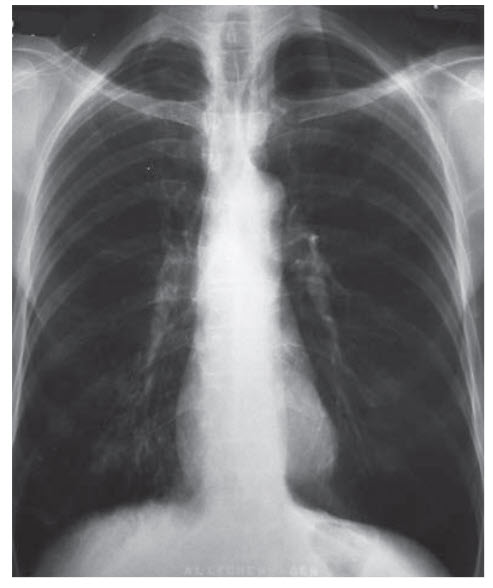

A 59-year-old woman with a history of hypertension and COPD presents to the hospital with shortness of breath. She recently visited her grandchildren and noticed several days later that her chronic cough became worse with an increase in yellow sputum production. She has also had to decrease her activities because of worsening dyspnea with any exertion. Her medications include hydrochlorothiazide, tiotropium, and inhaled albuterol and ipratropium as needed. She has a temperature of 37.6°C, blood pressure of 138/88 mmHg, heart rate of 96 beats per minute, respiratory rate of 28 breaths per minute, and oxygen saturation of 87% on room air. She is anxious and is using respiratory accessory muscles to breathe. There is hyper-resonance to percussion along both lung fields with wheezes and rhonchi heard bilaterally. Cardiac examination, as well as the rest of the physical examination, is unremarkable. The patient is admitted and her chest x-ray is shown in Figure below.